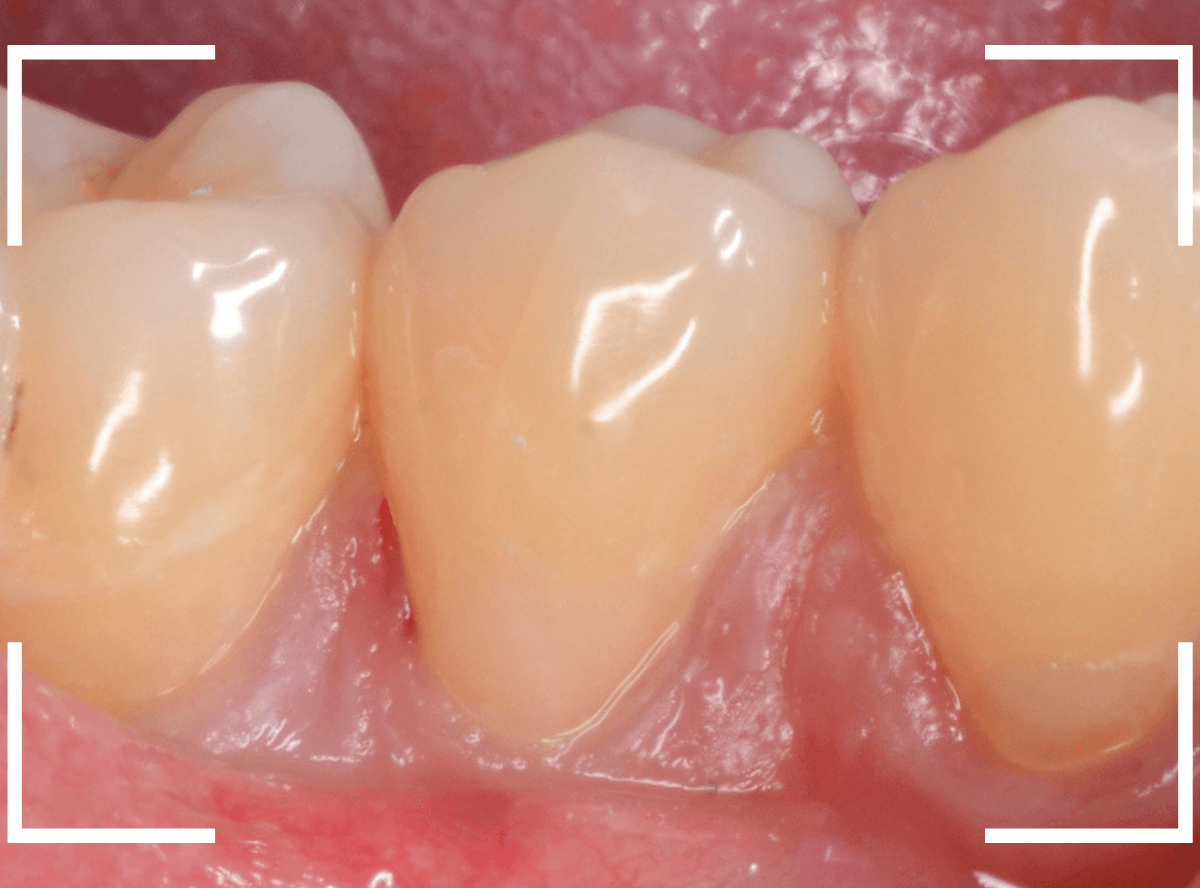

時々、下の奥歯がしみるという症状で、久しぶりに来院された患者さんです。

風を当てる機械でしみる場所を探ってみると、歯の付け根あたりでとても反応がありました。

典型的な知覚過敏といっていいでしょう。

先ほどの画像ではよくわかりづらかったですが、しみる部分を上から見てみると、少し凹んでるのがわかりますでしょうか。

これは、過度な歯ブラシや歯ぎしりなどが原因で歯の側面が摩耗している状態です。

何も感じない方も多く、その場合はあえて何もしない事も多いのですが、今回のように、大きな知覚過敏症状が出てしまう事もあります。

今回のように目に見えて凹んでる部分が見られる場合は、対処が簡単な事が多いです。